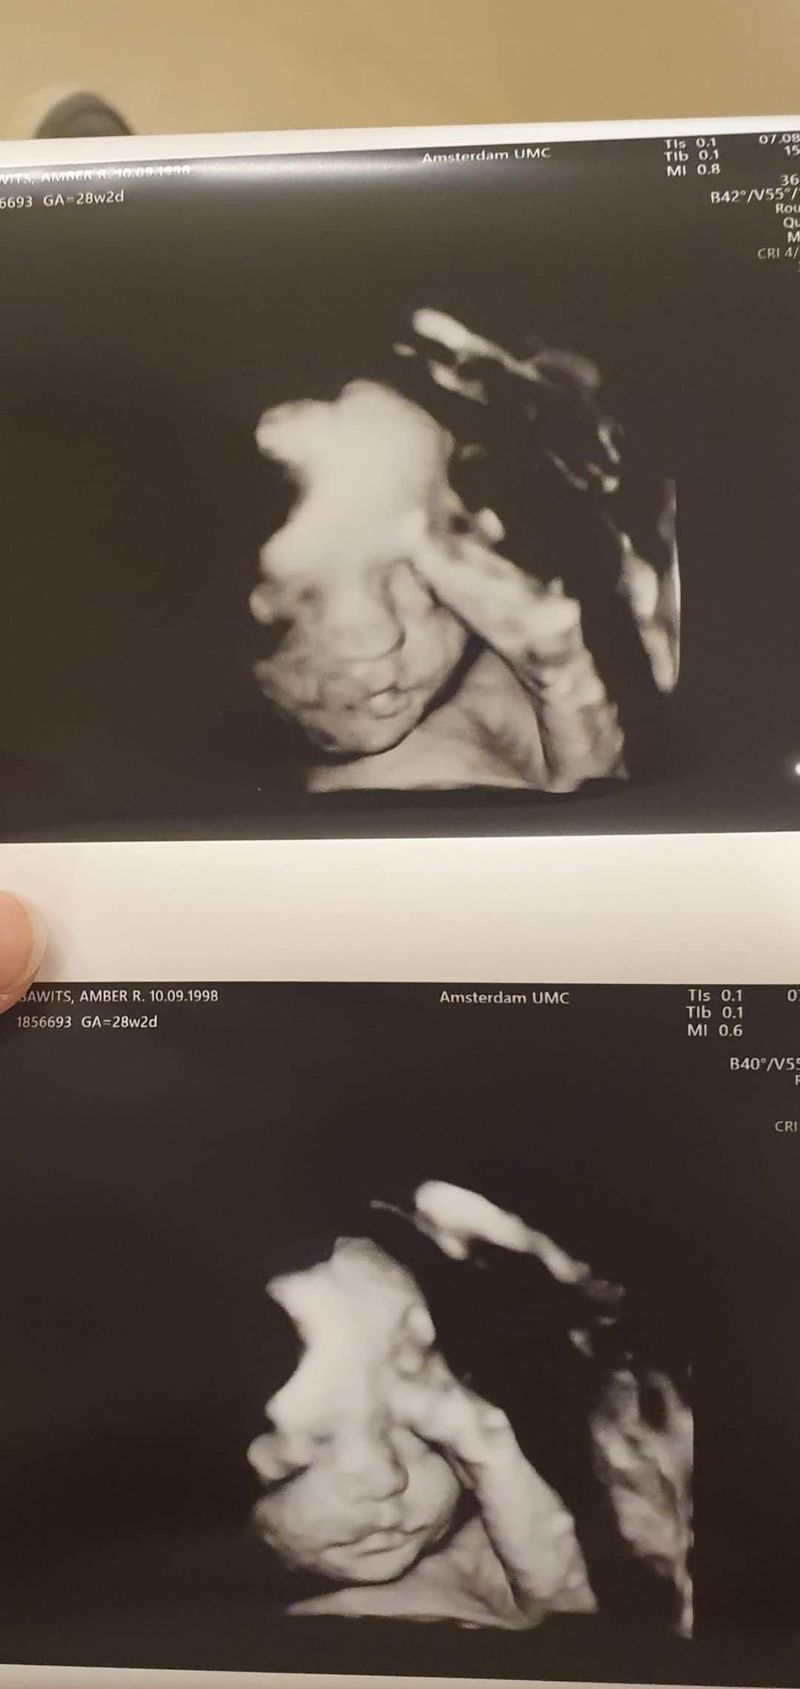

Er werden afwijkingen gevonden op de echo

Toen uiteindelijk alles weer een beetje normaal en rustig was, kochten wij ons droomhuis. Ik raakte weer zwanger en na alle ellende van afgelopen jaar was het wel tijd voor weer een beetje positieve energie. We kregen de sleutel en de dag daarna hadden we de 20-weken echo. Omdat het coronatijd was, mocht mijn vriend niet mee naar de echo. Ik vond dat niet erg, omdat ik daar geen gekke dingen verwachtte. Toch was de uitslag anders. Lynn bleek veel te klein, maar wel in verhouding, waardoor er werd gezegd dat het waarschijnlijk wel mee zal vallen. Toch moesten we voor controle even langs het ziekenhuis. Toen daar de GUO hele afwijkende resultaten gaf, moesten wij door naar het VUMC. Op dat moment was ik al bijna 22 weken zwanger en je mocht tot 24 weken de zwangerschap afbreken. We besloten een vruchtwaterpunctie te doen, ook al zou de uitslag waarschijnlijk te laat komen.

Het Silverrussel Syndroom

Ik ben toen alle studies gaan lezen. “Welke genen en mutaties kunnen dit beeld veroorzaken”, vroeg ik me hardop af. Dagenlang heb ik alles uitgezocht. Uiteindelijk kwam ik bij een studie waar ze bij muizen het hmga2-gen hadden gemanipuleerd. Dit was van alles wat ik had gelezen het meest positieve. Er was alleen niet veel over bekend bij mensen. Uiteindelijk werden wij gebeld door de klinisch geneticus. Hij vertelde dat er een afwijking was gevonden in het Hmga2-gen! Ik had hier ondertussen al super veel over gelezen en zij vertelde dat zij ook niet meer had kunnen vinden dan ik. Lynn haar mutatie is nog nooit eerder gezien. Wel kon het hmga2-gen zorgen voor het Silverrussel Syndroom. Daar had ik ook al veel over gelezen en dit durfden we aan.

Toen we besloten de zwangerschap door te zetten, bleef het spannend. We moesten naar het Erasmus in Rotterdam voor extra onderzoeken en 3d-echo’s. Het plan was dat ik daar zou gaan bevallen, maar nadat we er een paar keer waren geweest, voelde het voor mij toch niet goed. We kregen het idee dat wij vooral interessant waren vanwege de nieuwe mutatie en niet dat ons kindje daar beter af was. Nadat ik daarover had gebeld, kregen we een nogal kortaf mailtje dat we dan in het VU konden bevallen. Gelukkig toch dichtbij huis! De weken tot aan de bevalling moest ik om de dag naar het Vu voor een CTG en echo. Omdat de baby al veel te klein was, wilden ze zeker weten dat mijn placenta niet achteruit ging, de kleine had immers geen reserves. Dit was best een opgave, omdat ik thuis ook nog een dreumes had. Gelukkig kon zij elke keer naar mijn ouders die redelijk dichtbij het VU wonen.